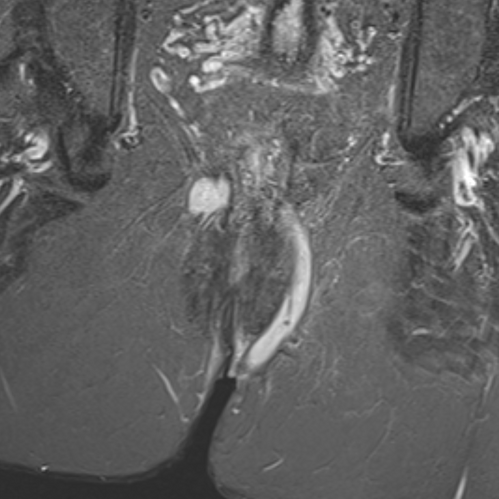

Advancing care for perianal fistulas

Exploring the challenges of perianal fistulas in Crohn’s disease and how new imaging and trial endpoints are advancing patient care.